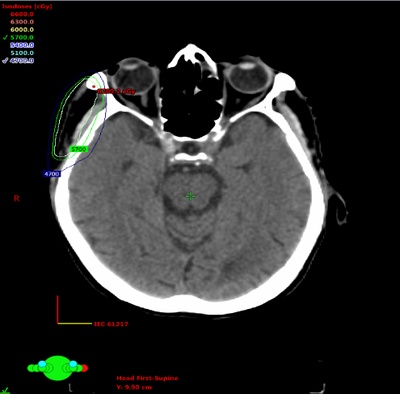

Primary Cutaneous Mucinous Adenocarcinoma of Facial Region Treated with Multimodality Therapy: Case Series of Rare Malignancy

Niladri Roy, Arnab Kumar Ghosh, Bappaditya Chhatui, Sharmistha Debnath, Alakananda Choudhury, Justice Mazumdar, Janmenjoy Mondal, Snigdha Hazra